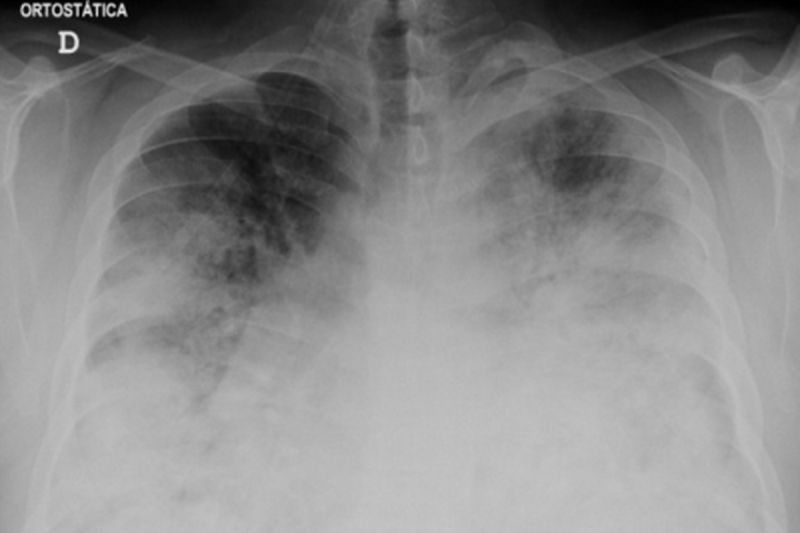

Penampakan hasil Rontgen bagian dada pada kasus Legionellosis yang parah saat masuk ke unit gawat darurat. (Wikimedia Commons/Jacob Ramos Morgado)Elshinta.com - Jumlah kematian akibat penyakit Legionnaires di Polandia tenggara pada Rabu (30/8) naik menjadi 16 orang, menurut otoritas kesehatan setempat. Penyakit Legionnaires adalah jenis radang paru-paru atau pneumonia yang disebabkan oleh bakteri legionella.